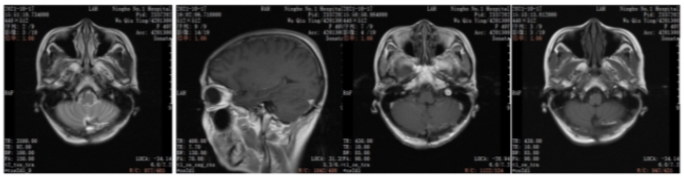

2022年5月颅脑增强MRI:左侧小脑肿瘤切除术后改变。

疗效评价CR,继续维持曲妥珠单抗(汉曲优)+吡咯替尼+卡培他滨治疗方案

图3.颅脑增强MRI